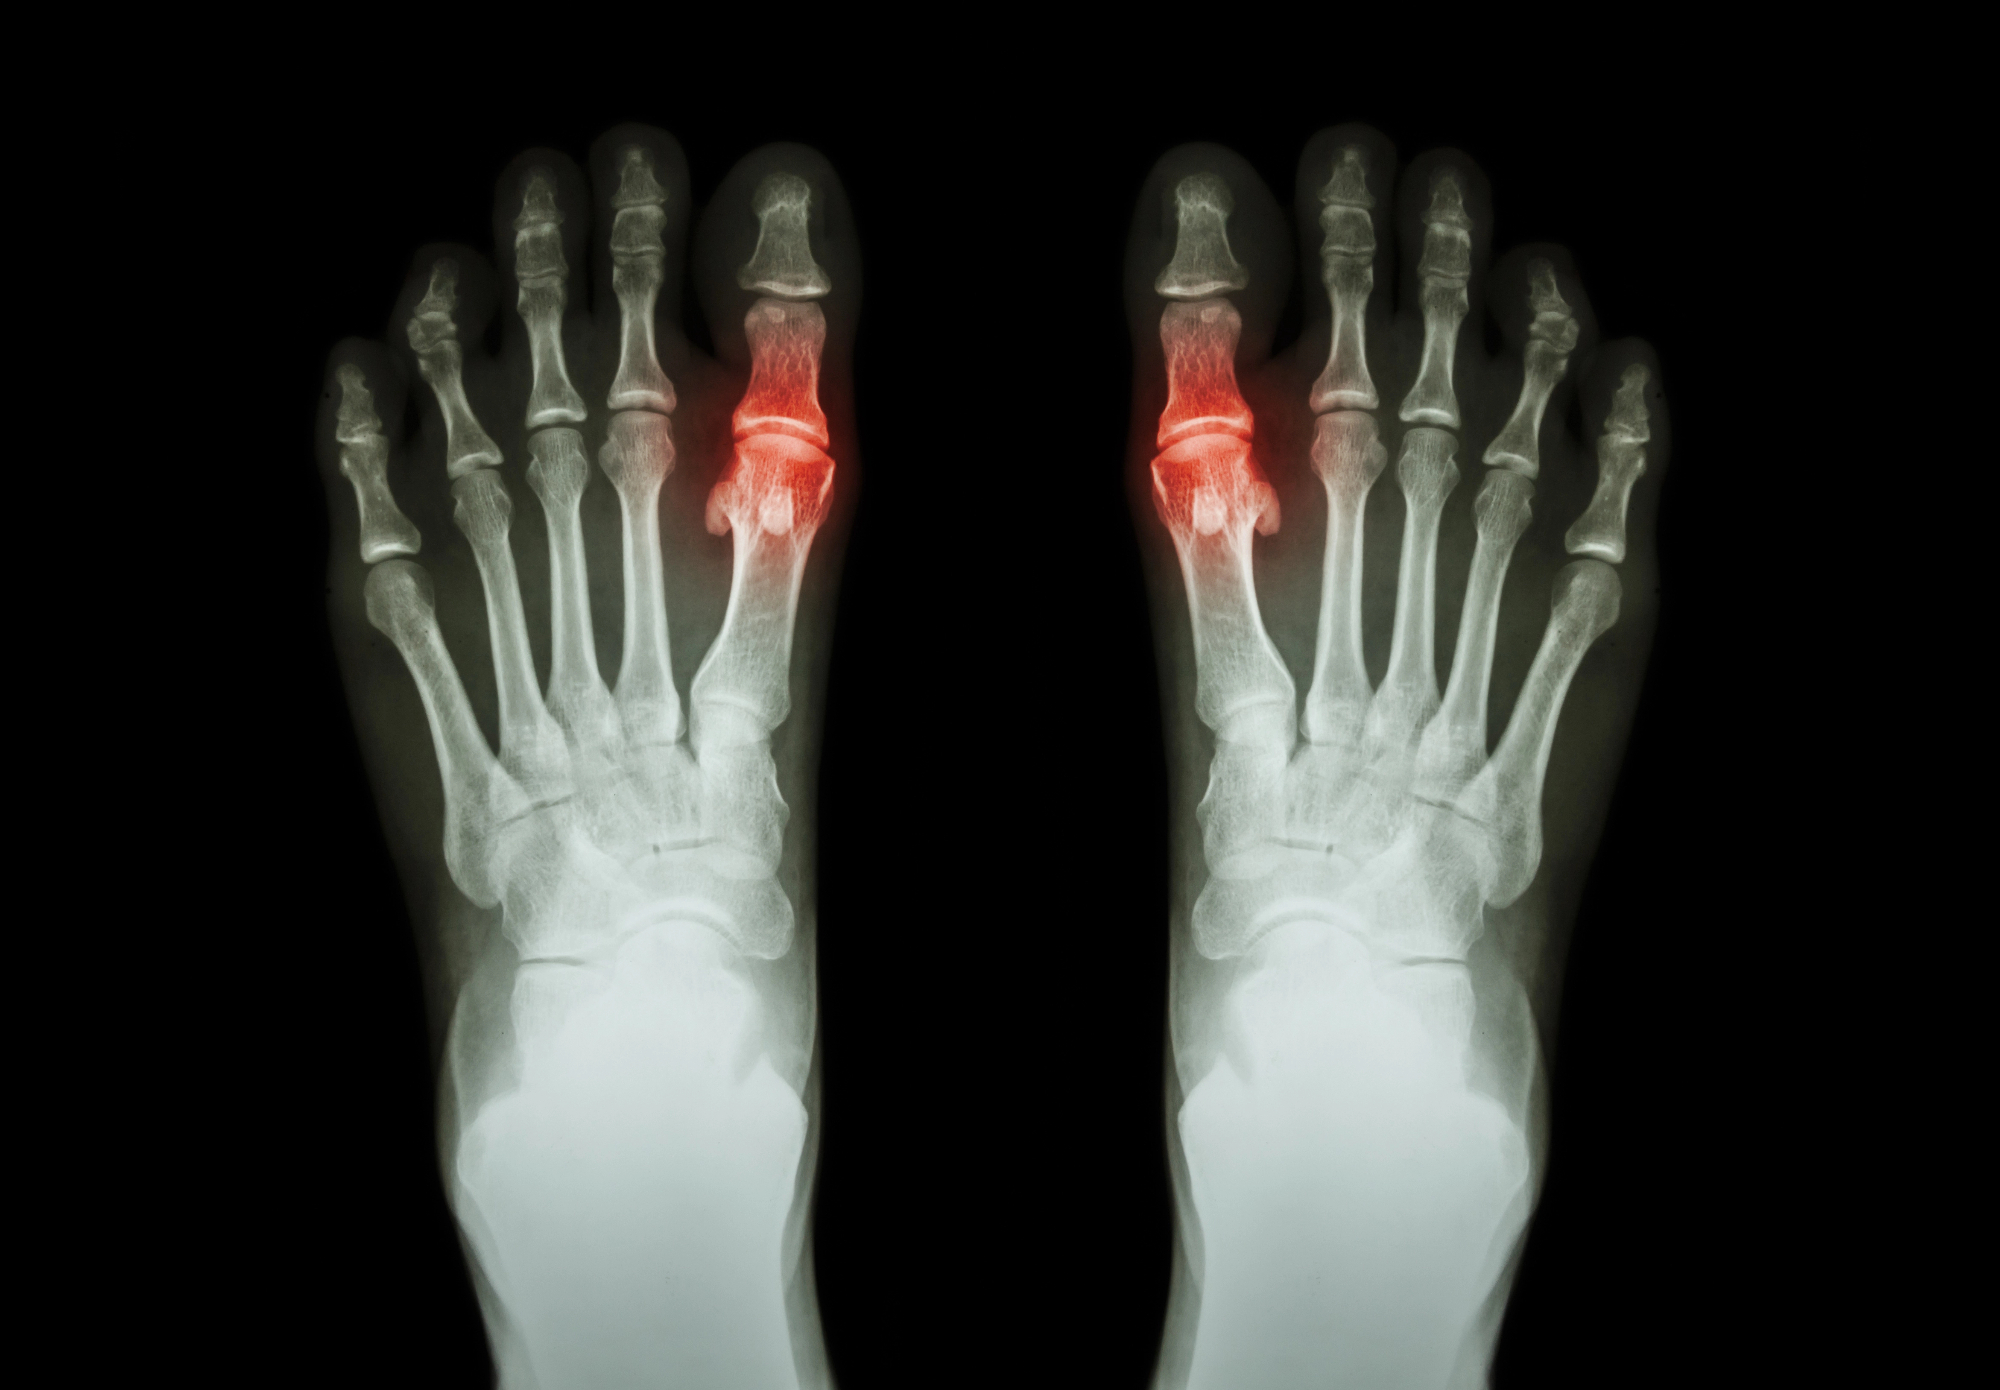

Ko sem obiskala babico po res dolgem času, sem zelo hitro ugotovila, da ne more normalno hoditi. Videla sem, da jo nekaj res močno boli, saj ni morala popolnoma stopiti na nogo. Najprej sem pomislila, da ima morda kaj zvito ali pa da si je morda celo kaj zlomila. Takoj sem jo vprašala, saj sem želela ugotoviti, kaj je narobe, zato da ji lahko na nek način pomagam. Rekla mi je besedo putika. Putika je definitivno nekaj, česar nisem imela v glavi in nisem razmišljala v to smer, ampak vedela sem, da je to problem, ki ga lahko rešimo. Najprej sem definitivno pomislila na protivnetna zdravila, saj sem vedela, da bi to lahko vsaj malo olajšalo bolečino. Vedela pa sem, da bo moja babica morala spremeniti svoj način življenja in da bo morala malce paziti tako na prehrano kot tudi na svoje gibanje.

Vem, da v zadnjih letih res ni poskrbela za svoje zdravje in ravno zato je prišlo do nečesa takšnega, kot je na primer putika. Babica se je zavedala tega in hvala bogu je svoje zdravje vzela v svoje roke. Bila sem zelo ponosna nanjo. Poklicala sem tudi zdravnika ter ga vprašala, kaj bi še lahko naredili, in on mi je podal nekaj nasvetov, ki sem jih predala naprej svoji babici. Bila sem zelo vesela, ko sem videla, da je te nasvete vzela resno, saj že naslednjič, ko sem bila pri njej, je bila moja babica mnogo bolje. Rekla je, da je res začela skrbeti za svoje zdravje in to se je res poznalo. Pri uričnem artritisu (putiki) pomaga tudi dovolj hidracije, omejitev živil z veliko purinov ter nežno, redno gibanje. Za dodatne nasvete o tem, kaj je urični artritis in kako ga obvladovati, sem obiskala stran Kirurgija Roke, kjer so jasno opisani simptomi, zdravljenje ter priporočila za prehrano in gibanje. Res sem zelo ponosna nanjo in bila sem zelo vesela, da sem jo takrat vprašala, kaj je narobe, saj sem lahko tako tudi na nek način pomagala. Seveda si želim, da bi moja babica živela dolgo in lepo življenje brez kakršnih koli bolečin. In če smo lahko ta problem rešili, bomo lahko rešili katerikoli problem, ki nas bo pričakal.